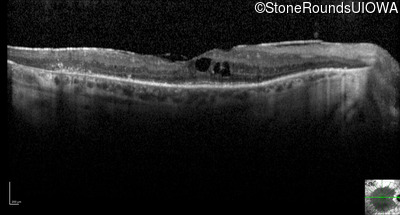

Optical Coherence Tomography - Left - 20/50 +1

Exemplar / OCT Stack

OCT Stack